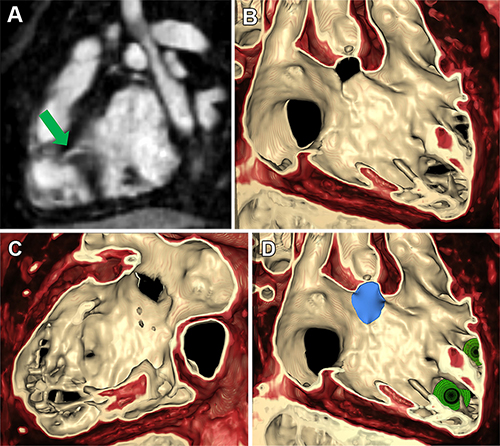

Figure 5. Volume rendering of multiphase steady-state imaging with contrast enhancement (ie, MUSIC) from ferumoxytol-enhanced cardiac MRI in a 4-year-old male patient with severe aortic insufficiency (patient 1) to inform valve repair. (A) Axial multiplane reconstruction in diastole. (B) Volume rendering from axial view in diastole. (C) Axial multiplane reconstruction in systole. (D) Axial view of volume-rendered image with cutting plane through aortic valve in systole.